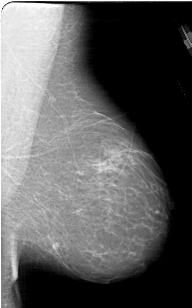

A_1830_1.RIGHT_CC

RIGHT_CC LINES 6091 PIXELS_PER_LINE 4021 BITS_PER_PIXEL 12 RESOLUTION 43.5 NON_OVERLAY